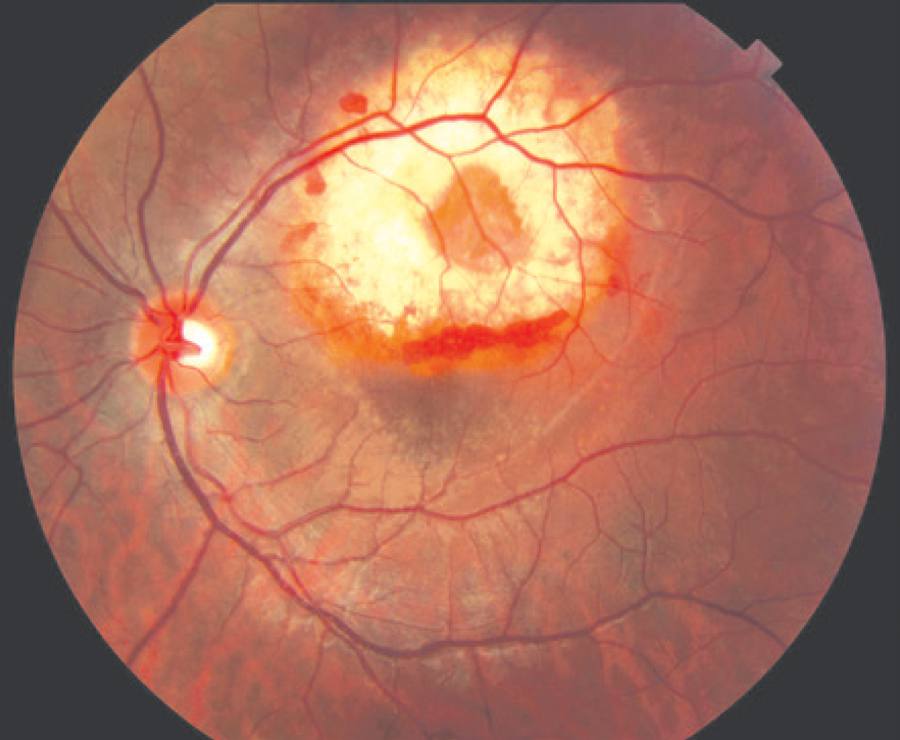

A 26-year-old Caucasian female experienced a sudden vision loss in her left eye. Her best corrected visual acuity was 20/20 in the right eye and 20/40 in the left eye. Her anterior segment examination was unremarkable. The fundus examination revealed a choroidal osteoma involving the entire macular area with subretinal hemorrhage and subretinal fluid in the fovea (Figure 2).

Figure 2 Color photograph of a choroidal osteoma with associated choroidal neovascularization. The neovascularization is located on the papillomacular bundle, and small spots of subretinal hemorrhage are noticed around it.

In both cases, the lesion had a yellow-white coloration with finger-like projections and pigmentary changes in the overlying RPE. The lesions were minimally elevated (<1.2 mm) and hyperreflective on ultrasonography, and both cases showed small areas of decalcification. Fluorescein angiography showed early patchy hyperfluorescence and late staining, and the choroidal neovascular membranes were found in the decalcified areas in both cases. We observed an angiographic leakage in the area of the membrane. On SD-OCT, the neovascular membrane was superior to the fovea and nasal to the fovea in cases 1 and 2, respectively; both cases had the presence of subretinal fluid.